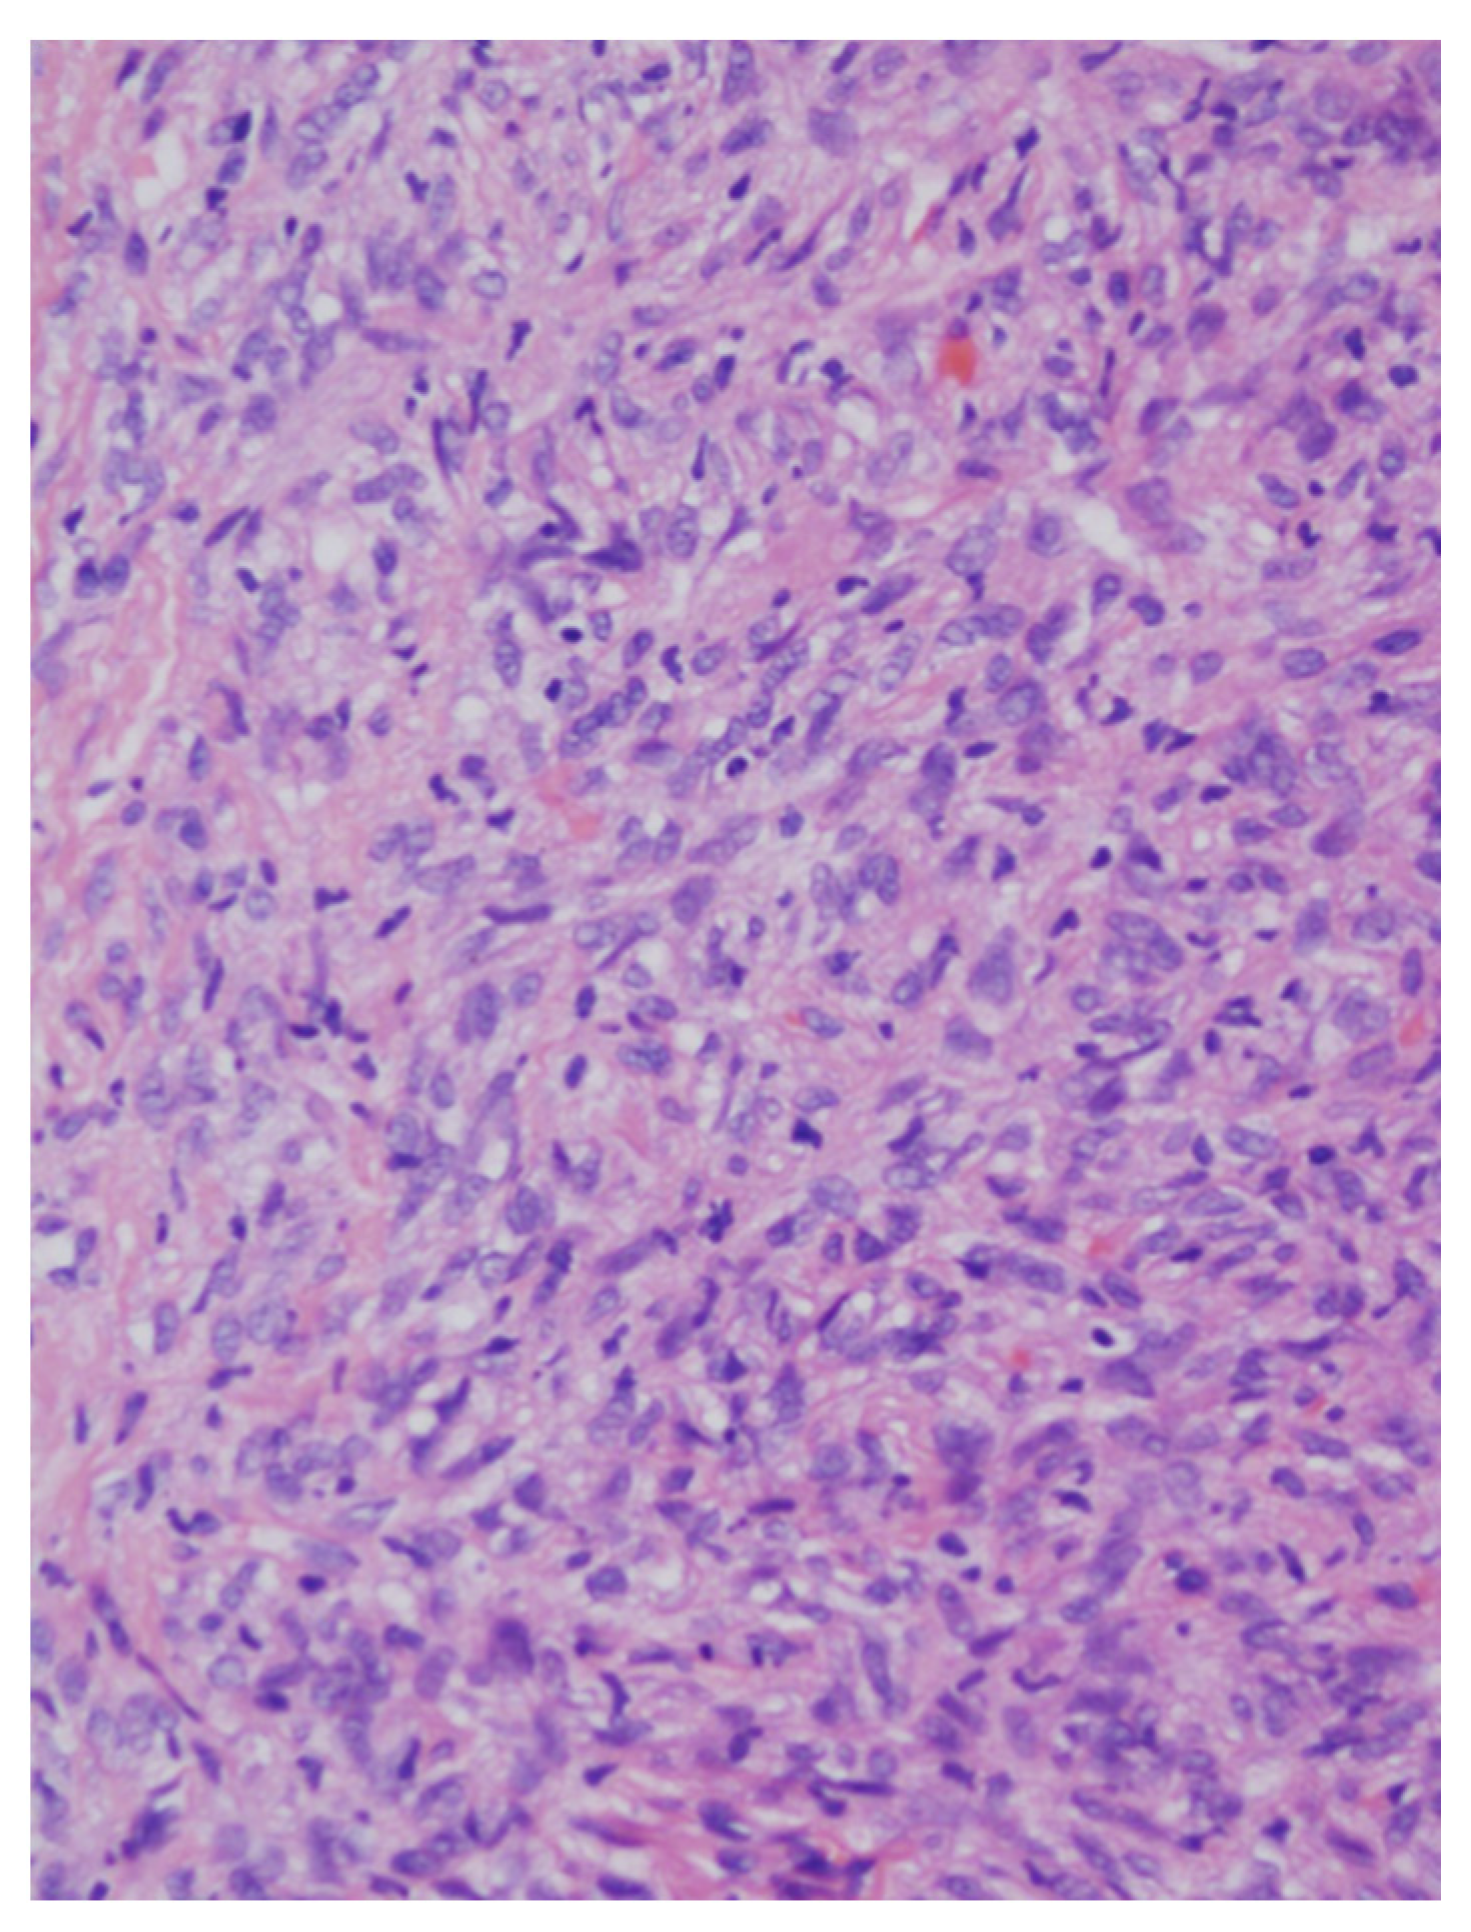

Routine microscopic examination in H&E-stained sections revealed a cellular tumor, with uniform and bland-looking spindle cells, without any organized pattern (patternless). The matrix was usually collagen-rich, and irregular blood vessels with a stag-horn morphology present within the tumor mass. All cases were well-circumscribed and non-infiltrative, only one case showed mild atypia, none exhibited necrosis, and mitotic activity was low in all cases, well below the threshold of 4 mitosis/10 high-power fields (HPF). Therefore, all of the cases in the present series conform with the criteria for low-risk for metastasis and recurrence [14,15].

Figure 3. Low magnification showing a cellular spindle cell tumor with a “patternless pattern”. Irregular branching vessels are visible. (hematoxylin and eosin (H&E) stained, original magnification ×40).

Figure 4. At a higher magnification the tumor cells are spindle-shaped, monomorphic, and bland-looking (H&E stained, original magnification ×200).